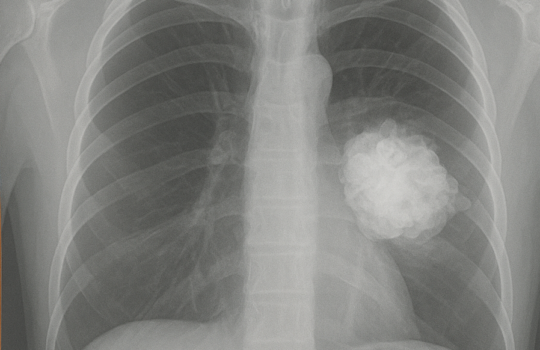

O Pemetrexede Dissódico é um medicamento usado no tratamento de alguns tipos de câncer, principalmente o mesotelioma pleural maligno e o câncer de pulmão de células não pequenas (CPCNP).